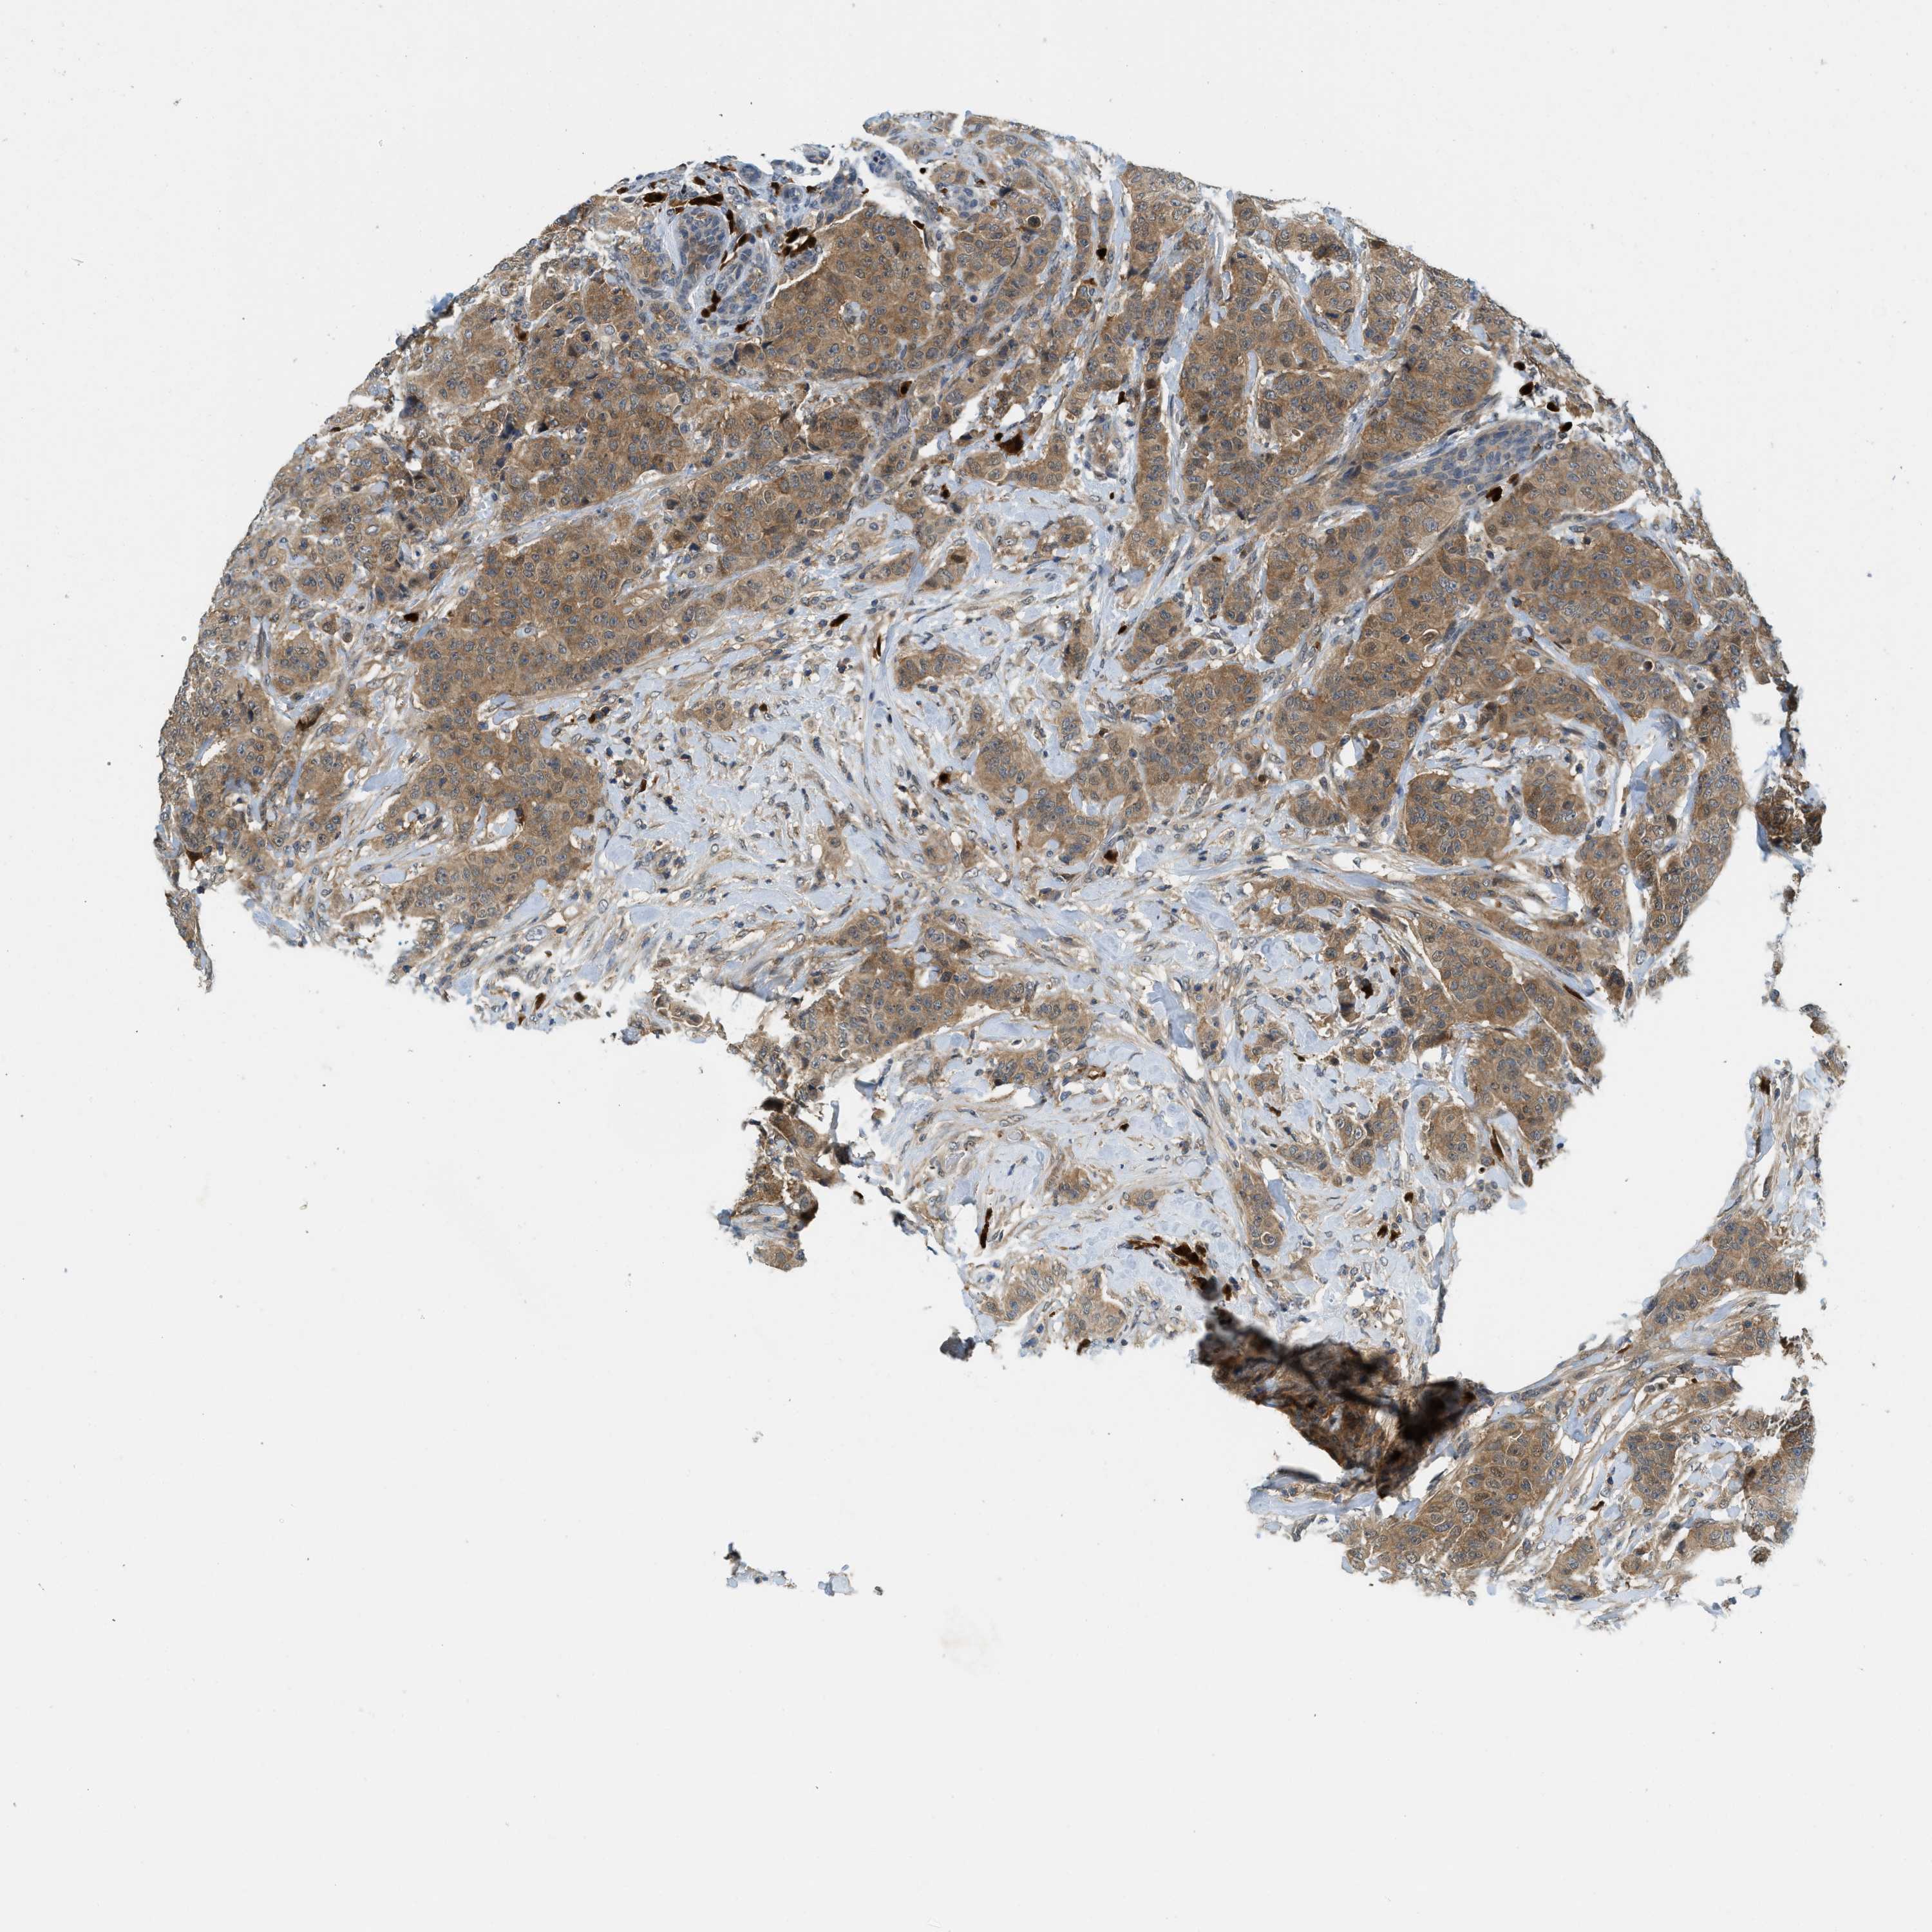

CANCER BREAST CANCER Show tissue menu

BRCA TCGA BRCA VALIDATION PROTEIN EXPRESSION